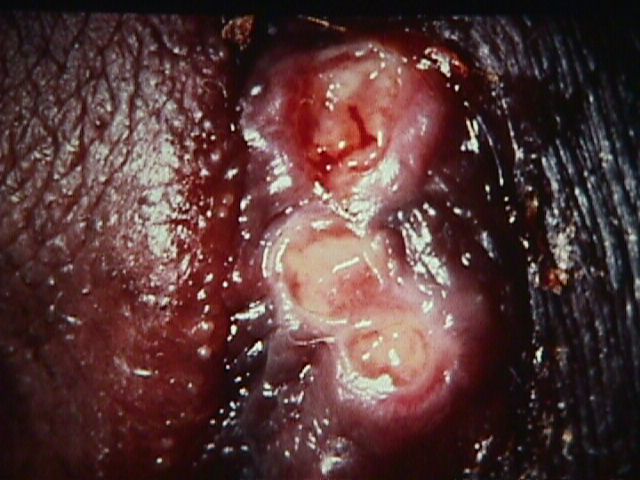

Vulvar ulcers are open sores that can occur on the vulva, the external female genitalia. These ulcers can be caused by a number of things, including infection, trauma, or autoimmune disease. Vulvar ulcers can be very painful and can make urination and sexual intercourse difficult. Treatment for vulvar ulcers depends on the underlying cause but may include topical or oral antiviral medication, antibiotics, or surgery.

There are a few different symptoms that are associated with vulvar ulcers. The first and most common symptom is pain. This can range from a dull ache to a sharp pain that can make it difficult to walk or sit. Other symptoms include itching, burning, and bleeding. In some cases, the ulcer may also cause a discharge. If you have any of these symptoms, it is important to see your doctor so they can properly diagnose and treat the ulcer.

A vulvar ulcer is a sore that forms on the vulva, the external female genital area. Vulvar ulcers can be painful and may make urinating and sexual intercourse difficult. They can also cause bleeding and discharge.